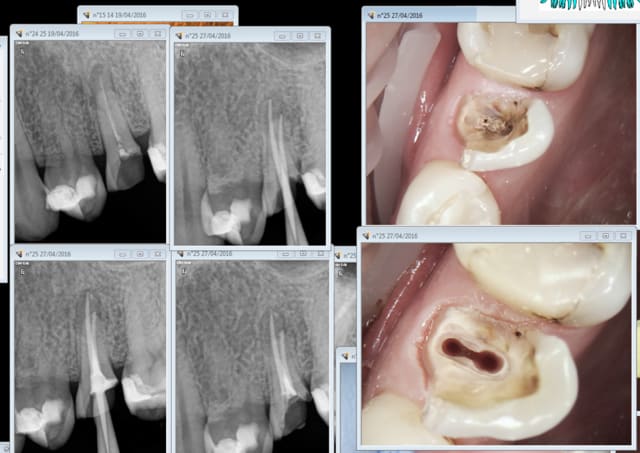

Merde il y avait une fistule . je m'en suis aperçu juste après la remise du devis pour l'ic coiffe. Ca ne se voit pas trop à la radio ? Je peux y aller sans risque d'indu ? Parce que voyez vous ca me fait chier d'avoir travaillé pour rien. -)

Capture d e cran 2016 04 27 19.08 - Eugenol

8tercecn7hisbbqbde2nil4nyxrw - Eugenol